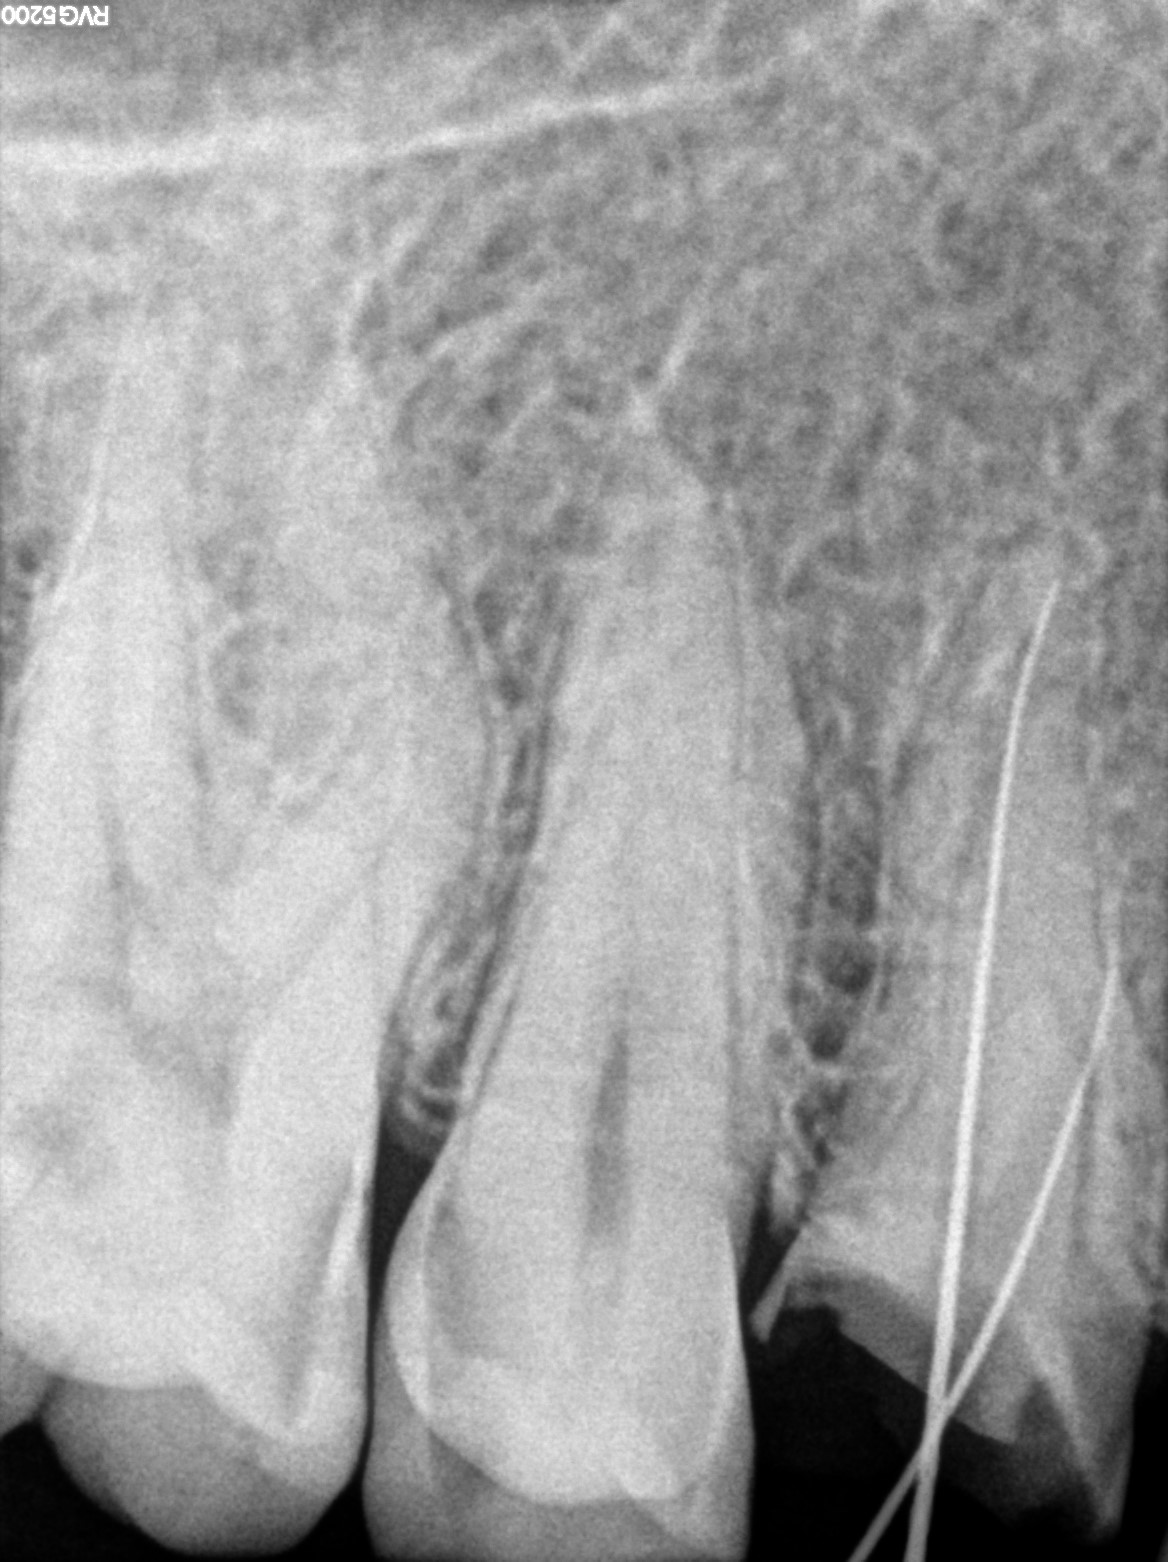

Dental Radiographs FHIR: DocumentReference · LOINC 24641-7

R55.jpg

24641-7